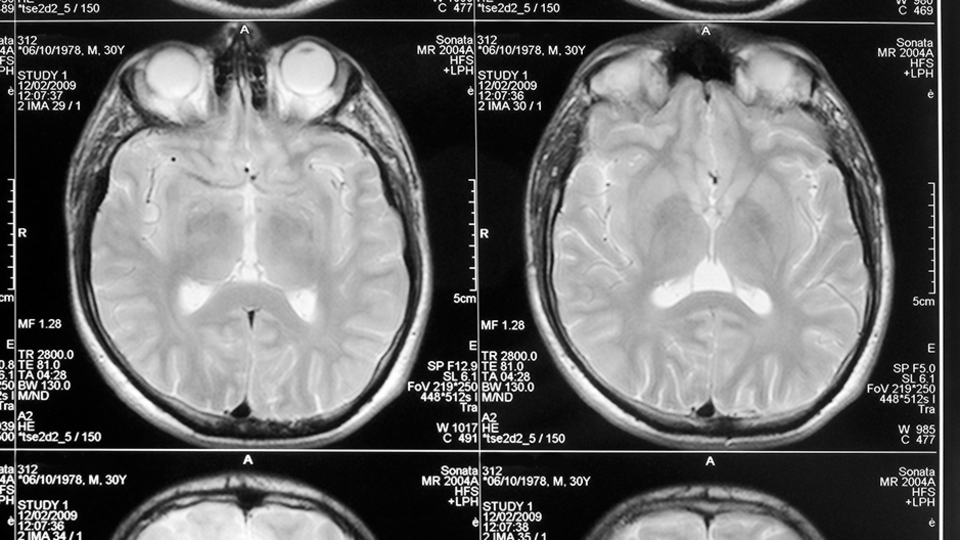

İngiliz gazete Daily Mail'de yer alan habere göre; sürekli epilepsi nöbetleri geçiren ve baş ağrısı çeken sekiz yaşındaki kız çocuğuna, beyninde kist olabileceği düşünülerek, steroid tedavisi verildi. Altı aydan sonra küçük kızın nefesi kesilmeye ve yürüyememeye başladı. Yapılan taramaların ardından minik kızın beyninde 100 tane tenya yumurtası olduğunu tespit ettiler. Beynindeki kurtçuklar çıkarıldıktan sonra küçük kız iyileşti ve yürümeye başladı.